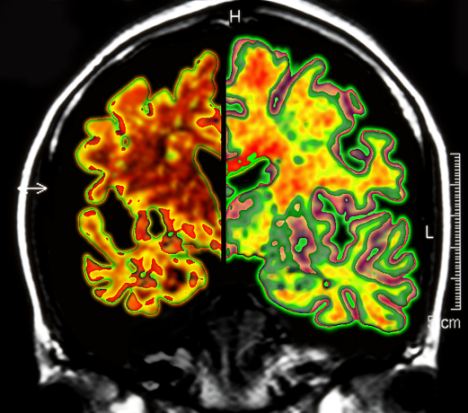

患有老年癡呆癥的大腦掃描圖

“銀河系中所存在的宇宙輻射會對宇航員的身體造成巨大傷害。”該項研究的主要作者、神經生物學和解剖學系教授克里·奧班寧介紹說,“眾所周知,輻射將會大大提高癌癥等疾病的發病率,不過我們的研究表明,當宇航員接觸到一定劑量的宇宙射線的輻射時,其大腦可能會受到傷害,進而導致老年癡呆癥。所以美國國家航空航天局(NASA)應該將此考慮到未來的太空任務中,控制宇航員在外太空的工作時間,以避免出現上述情況。”